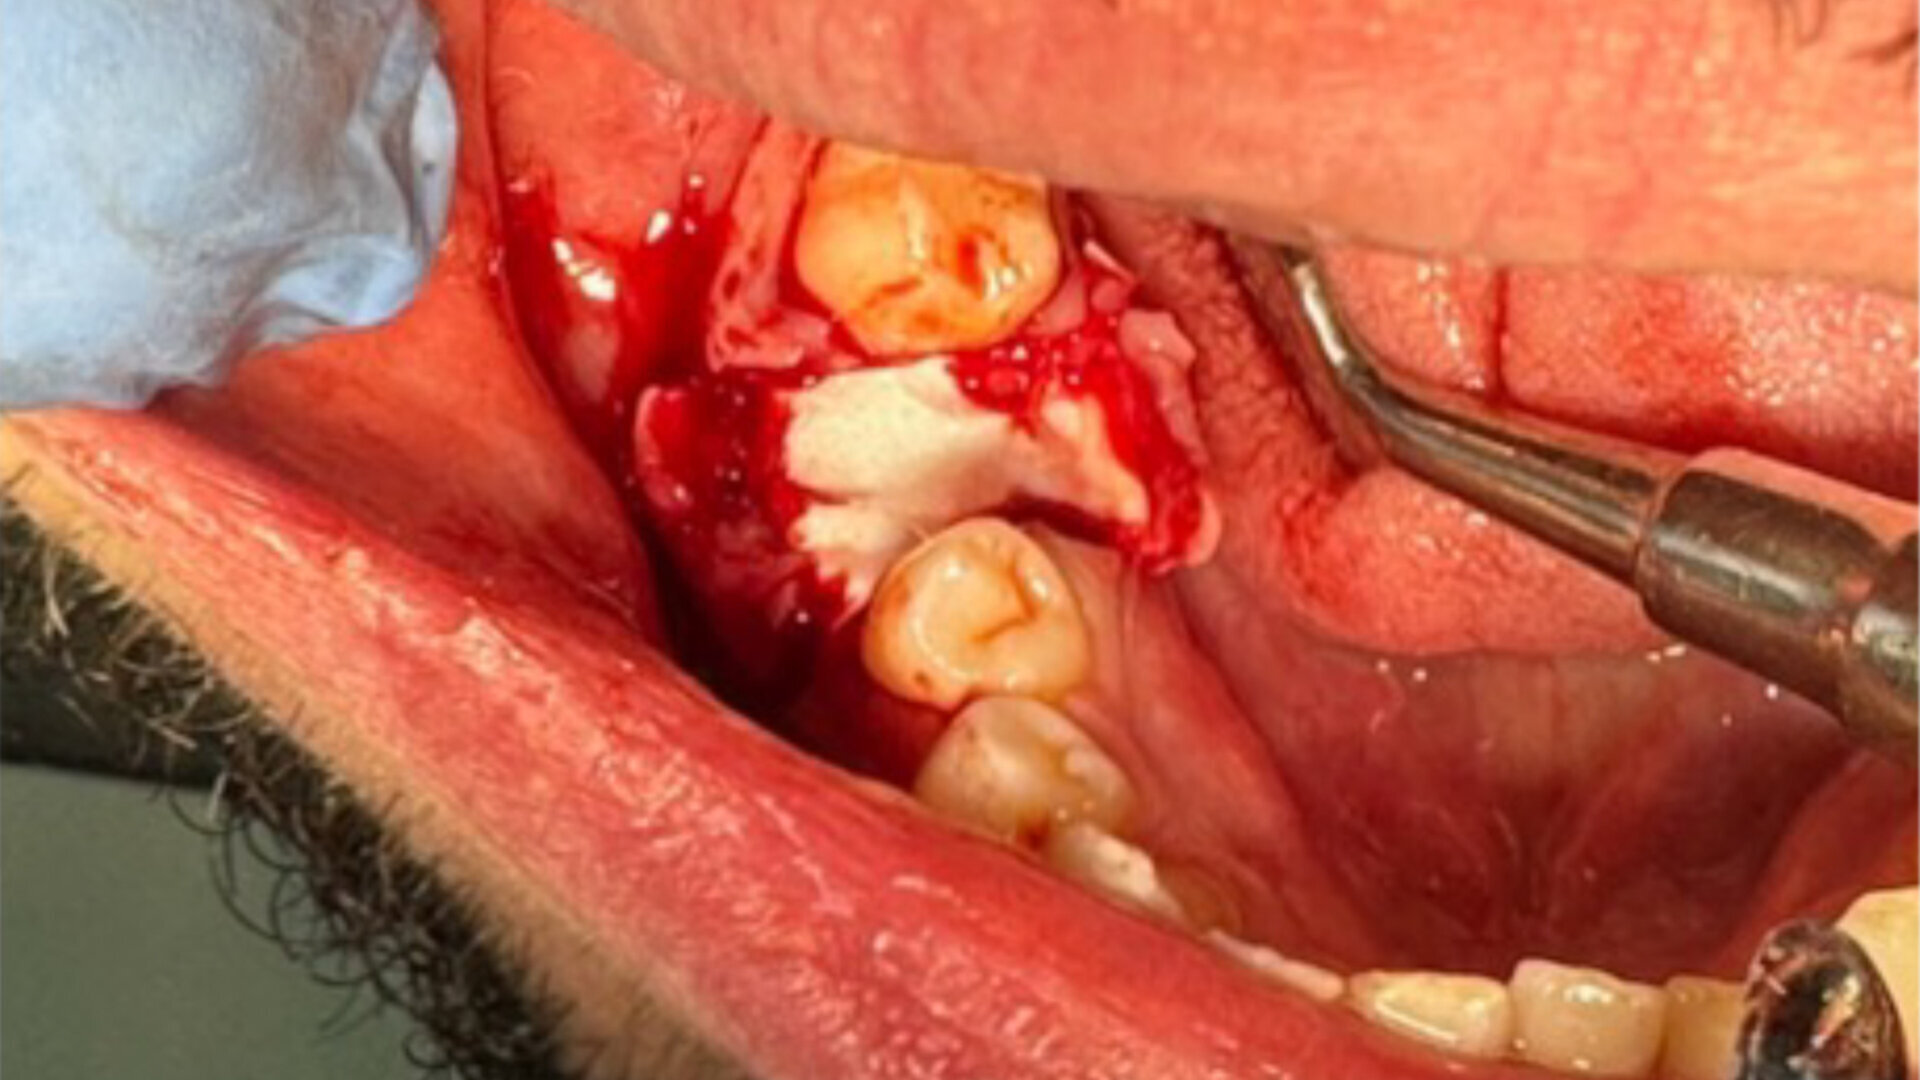

CBCT préimplantaire

Lors de la réouverture pour la pose de l’implant, nous avons pu constater que la hauteur de l’alvéole a été préservée, et la constitution de néo os alvéolaire de belle consistance nous a permis la pose de l’implant en toute sécurité (Figs. 9 et 10).

Fig. 9

Étapes de l’intervention implantaire